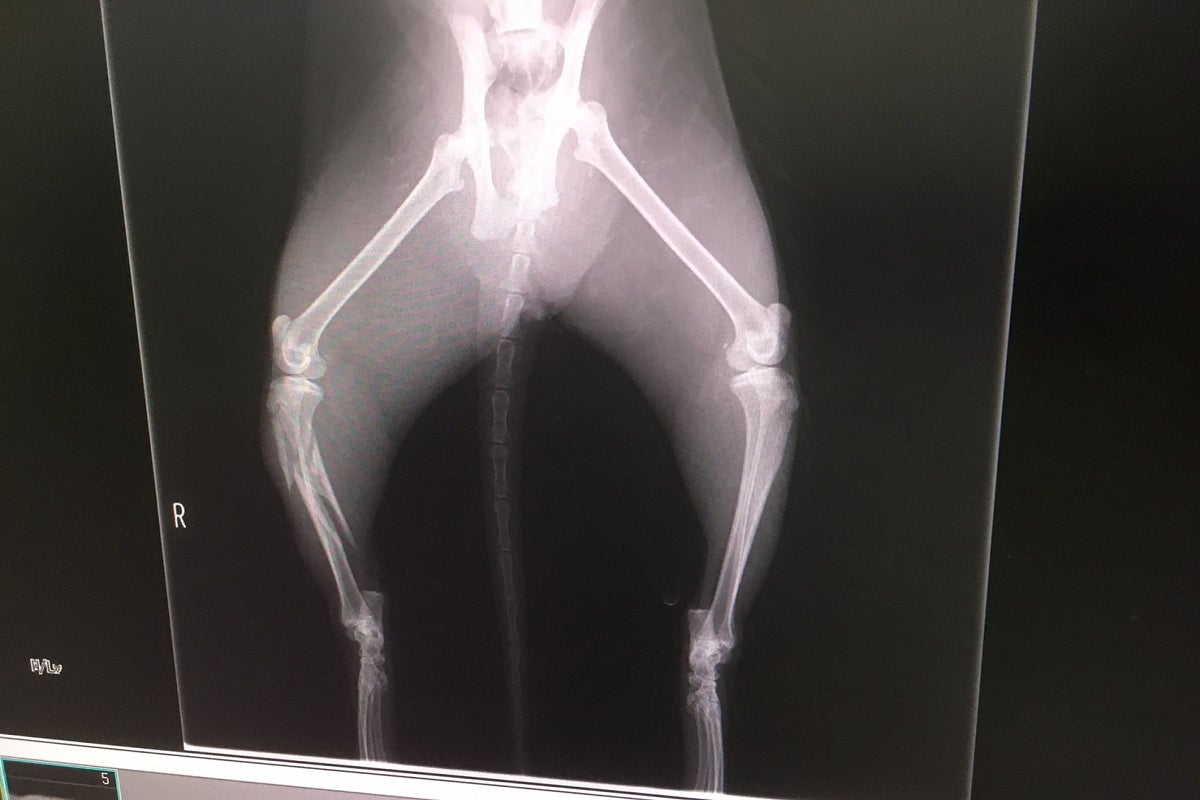

レントゲンでの診断の結果

骨盤骨折(腸を圧迫して排便できないかもしれない)

脛骨複雑骨折

重度の貧血

膿が溜まっている。

獣医師の診断は虐待ではなく事故だろう。膿の様子から事故してから1週間

くらいは経過しているだろう